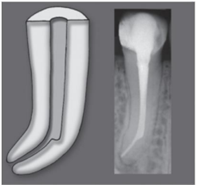

Um degrau é uma anomalia formada na parede

de um canal radicular antes de atingir o ápice e

sem qualquer conexão com o ligamento

periodontal. Sua ocorrência é mais comum nas

porções iniciais dos canais radiculares curvos.

A parede externa do canal sofre desgaste,

resultando na configuração de um plano

horizontal conhecido como degrau. Esse

incidente dificulta ou até mesmo impossibilita

o avanço do instrumento em direção apical no

canal radicular.